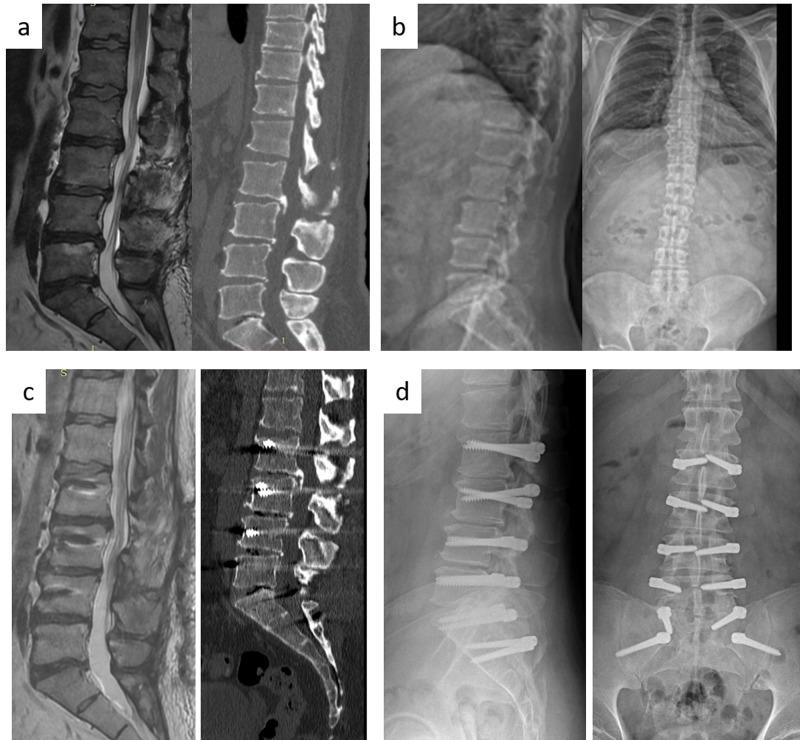

Background In this article, clinical satisfaction and radiological results are discussed in a series of patients where the iliac wings participate in dynamic stabilization. Dynamic stabilization is an effective alternative surgical treatment method, especially in clinical pictures that go with pain due to minor instabilities. Practically the unique surgical instrument used in multilevel instabilities is the Dynesys system. The most important drawback of the Dynesys system is that the S1 screws become loose in time. In this article, our aim is to find solution to S1 insufficiency by extension of the system to the iliac wings. Methods Nineteen patients (eight females, 11 males) with a mean age of 54.16 were included in the study. Patients had multilevel (level 2 and above) instability, iliac wings were included in the stabilized segments, and Visual Analog Scale (VAS) and Oswestry Disability Index (ODI) were used for patient follow-up. Results First year results showed a significant improvement in VAS and ODI. Regarding the complications, infection developed in one patient, loosening in the proximal iliac wing in one patient, and both S1 and iliac proximals in one patient, but no clinical findings were encountered. Conclusion When more than two levels of dynamic systems are used in chronic instability, especially in the elderly patients, S1 screws are loosened. In these patients, if the iliac bones are also included in stabilization, this problem is solved successfully. However unfortunately, Dynesys system does not have a screw suitable for the iliac bones.